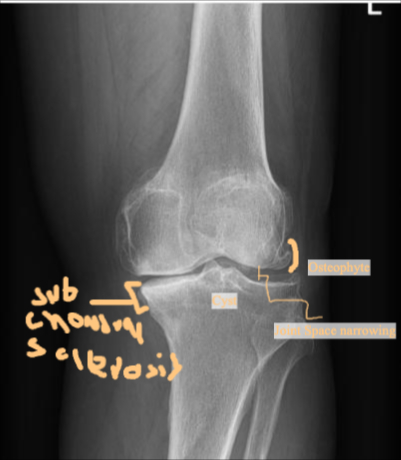

Reading an X-Ray of Osteoarthritic Knee Joint

Five Key Features

- Narrowing of the joint line

- Formation of osteophyte

- Subchondral sclerosis

- Subchondral cyst

- Joint deformity

X-ray AP Lateral Osteophyte formation - joint space narrowing - Subchondral cyst adn sclerosis - joint Varus deformity